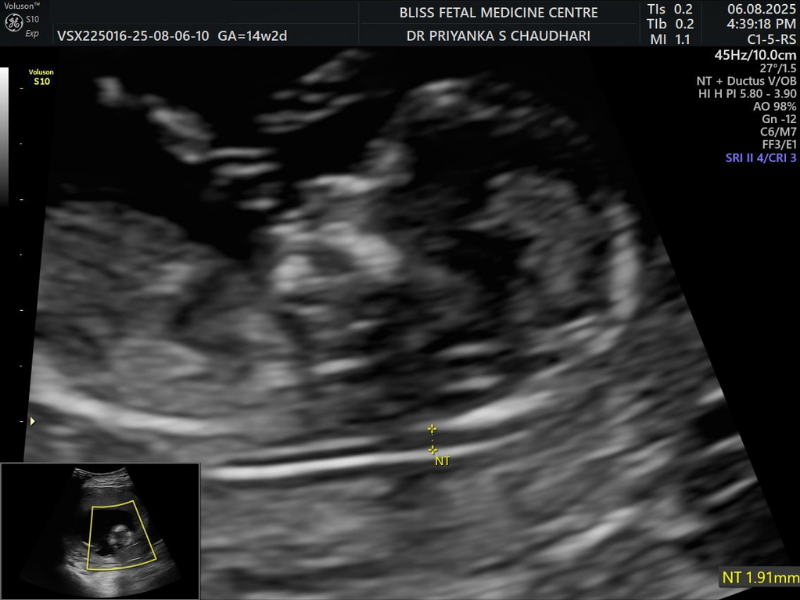

2. First Trimester (NT-NB) Scan

A Nuchal Translucency/Nasal Bone (NT-TB) Scan helps assess the risk of the baby having specific chromosomal abnormalities. The NT scan measures the space filled with fluid behind the neck of your unborn baby, while the NB scan helps determine the absence or presence of the nasal bone, which can indicate potential chromosomal issues.

When Is It Performed?

- It is performed between 11 and 14 weeks of pregnancy in the first trimester.

- It is recommended when a woman’s age, family history, lifestyle, etc, can increase risks.

- It can also be recommended if the previous tests show potential risks.